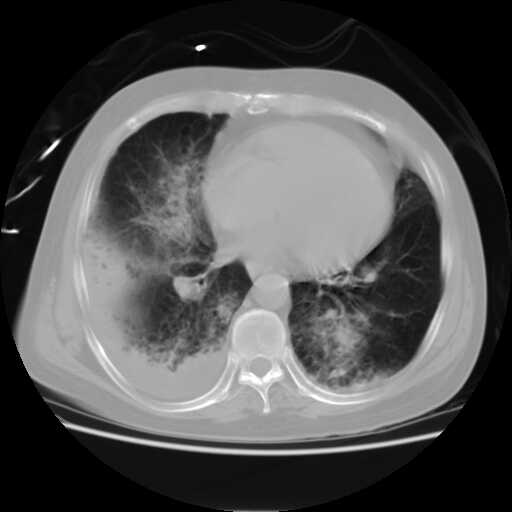

患者,男,60岁,病史如下:

2008.8.17ct

病变从8.11-8.17明显改变,增多,以蜂窝状改变为主,类蜂窝肺,似弥漫性肺泡癌,但是病变进展太快,不符合弥漫性细支气管肺泡癌。因此考虑为特殊微生物感染,多以霉菌类常见,建议细菌微生物学检查。

追踪结果,该病人已于2008.8.18日经抢救无效死亡.死于呼吸衰竭.具体病因不明,未作死体解剖.

疑点二:影象表现怪异,大片阴影内见多发筛孔征,如何解释.

间质为主,血管炎性水肿?